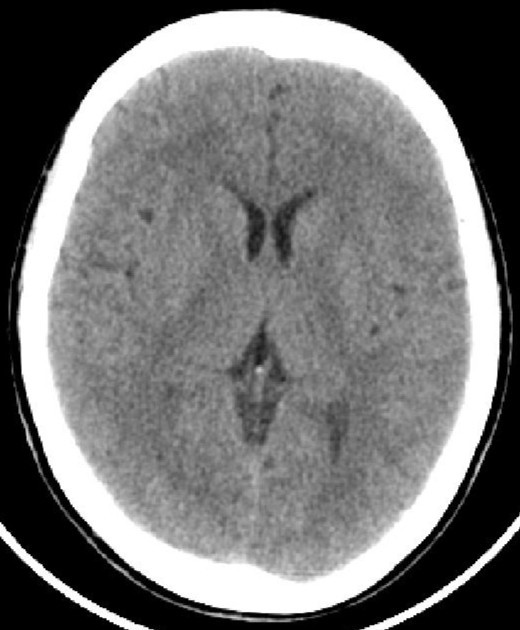

因為腦脊液的分泌、或循環(huán)、或吸收過程中出現(xiàn)障礙,則會產(chǎn)生腦積水。腦積水致腦脊液的容積增大,導(dǎo)致腦血流量及腦組織受壓并容積減少。臨床分類多樣:嬰幼兒腦積水和成人腦積水;高壓性腦積水和常壓性腦積水;腦室內(nèi)腦積水和腦外腦積水;癥狀性腦積水和無癥狀性腦積水;進行性腦積水和靜止性腦積水。比較常用的是按病因分類:交通性腦積水和阻塞性腦積水。其中交通性腦積水病因:腦脊液吸收功能障礙、蛛網(wǎng)膜顆粒發(fā)育不良、腦脊液成份改變或濃縮及腦脊液分泌過多;阻塞性腦積水病因:中腦水管狹窄或閉塞、Dandy-Walker綜合征、小腦扁桃體下疝畸形、炎癥或出血、顱內(nèi)占位性病變等。臨床癥狀:嬰幼兒有發(fā)育延遲、頭顱增大、行走障礙等;成人可有神志及精神變差、記憶力下降、頭痛頭暈、行走困難或二便失控等。頭顱CTMR可以明確診斷及辨別病因。治療主要以手術(shù)治療為主。絕大多數(shù)患者愈合良好。(神經(jīng)外科 龍青山)

正常頭顱CT          頭顱CT示腦積水